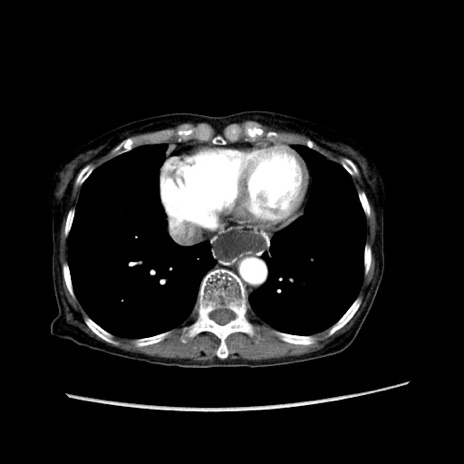

症例25(横断像)

【症例】80歳代女性

【主訴】胸のつかえ感

【現病歴】約9時間前に食後から胸のつかえた感じあり、嘔吐あり、来院。

【既往歴】胃癌(全摘)、胆摘、虫垂炎

【身体所見】心窩部に圧痛あり、反跳痛なし。

【データ】WBC 5700、CRP 0.05